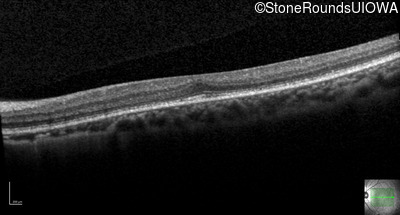

Optical Coherence Tomography - Right - 20/25

Exemplar / OCT Stack